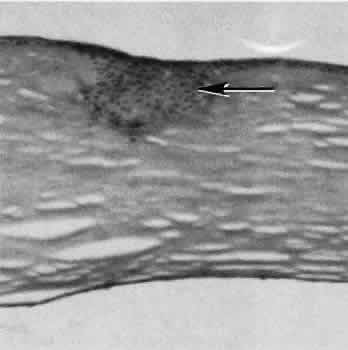

Fig. 9. A. Well-healed scar (between arrows) barely perceptible in photomicrograph. B. Higher magnification of scar. Migrating corneal endothelium has closed the posterior hiatus of the wound in Descemet's membrane (arrow). (Hematoxylin-eosin stain; A, × 33; B, × 82.)